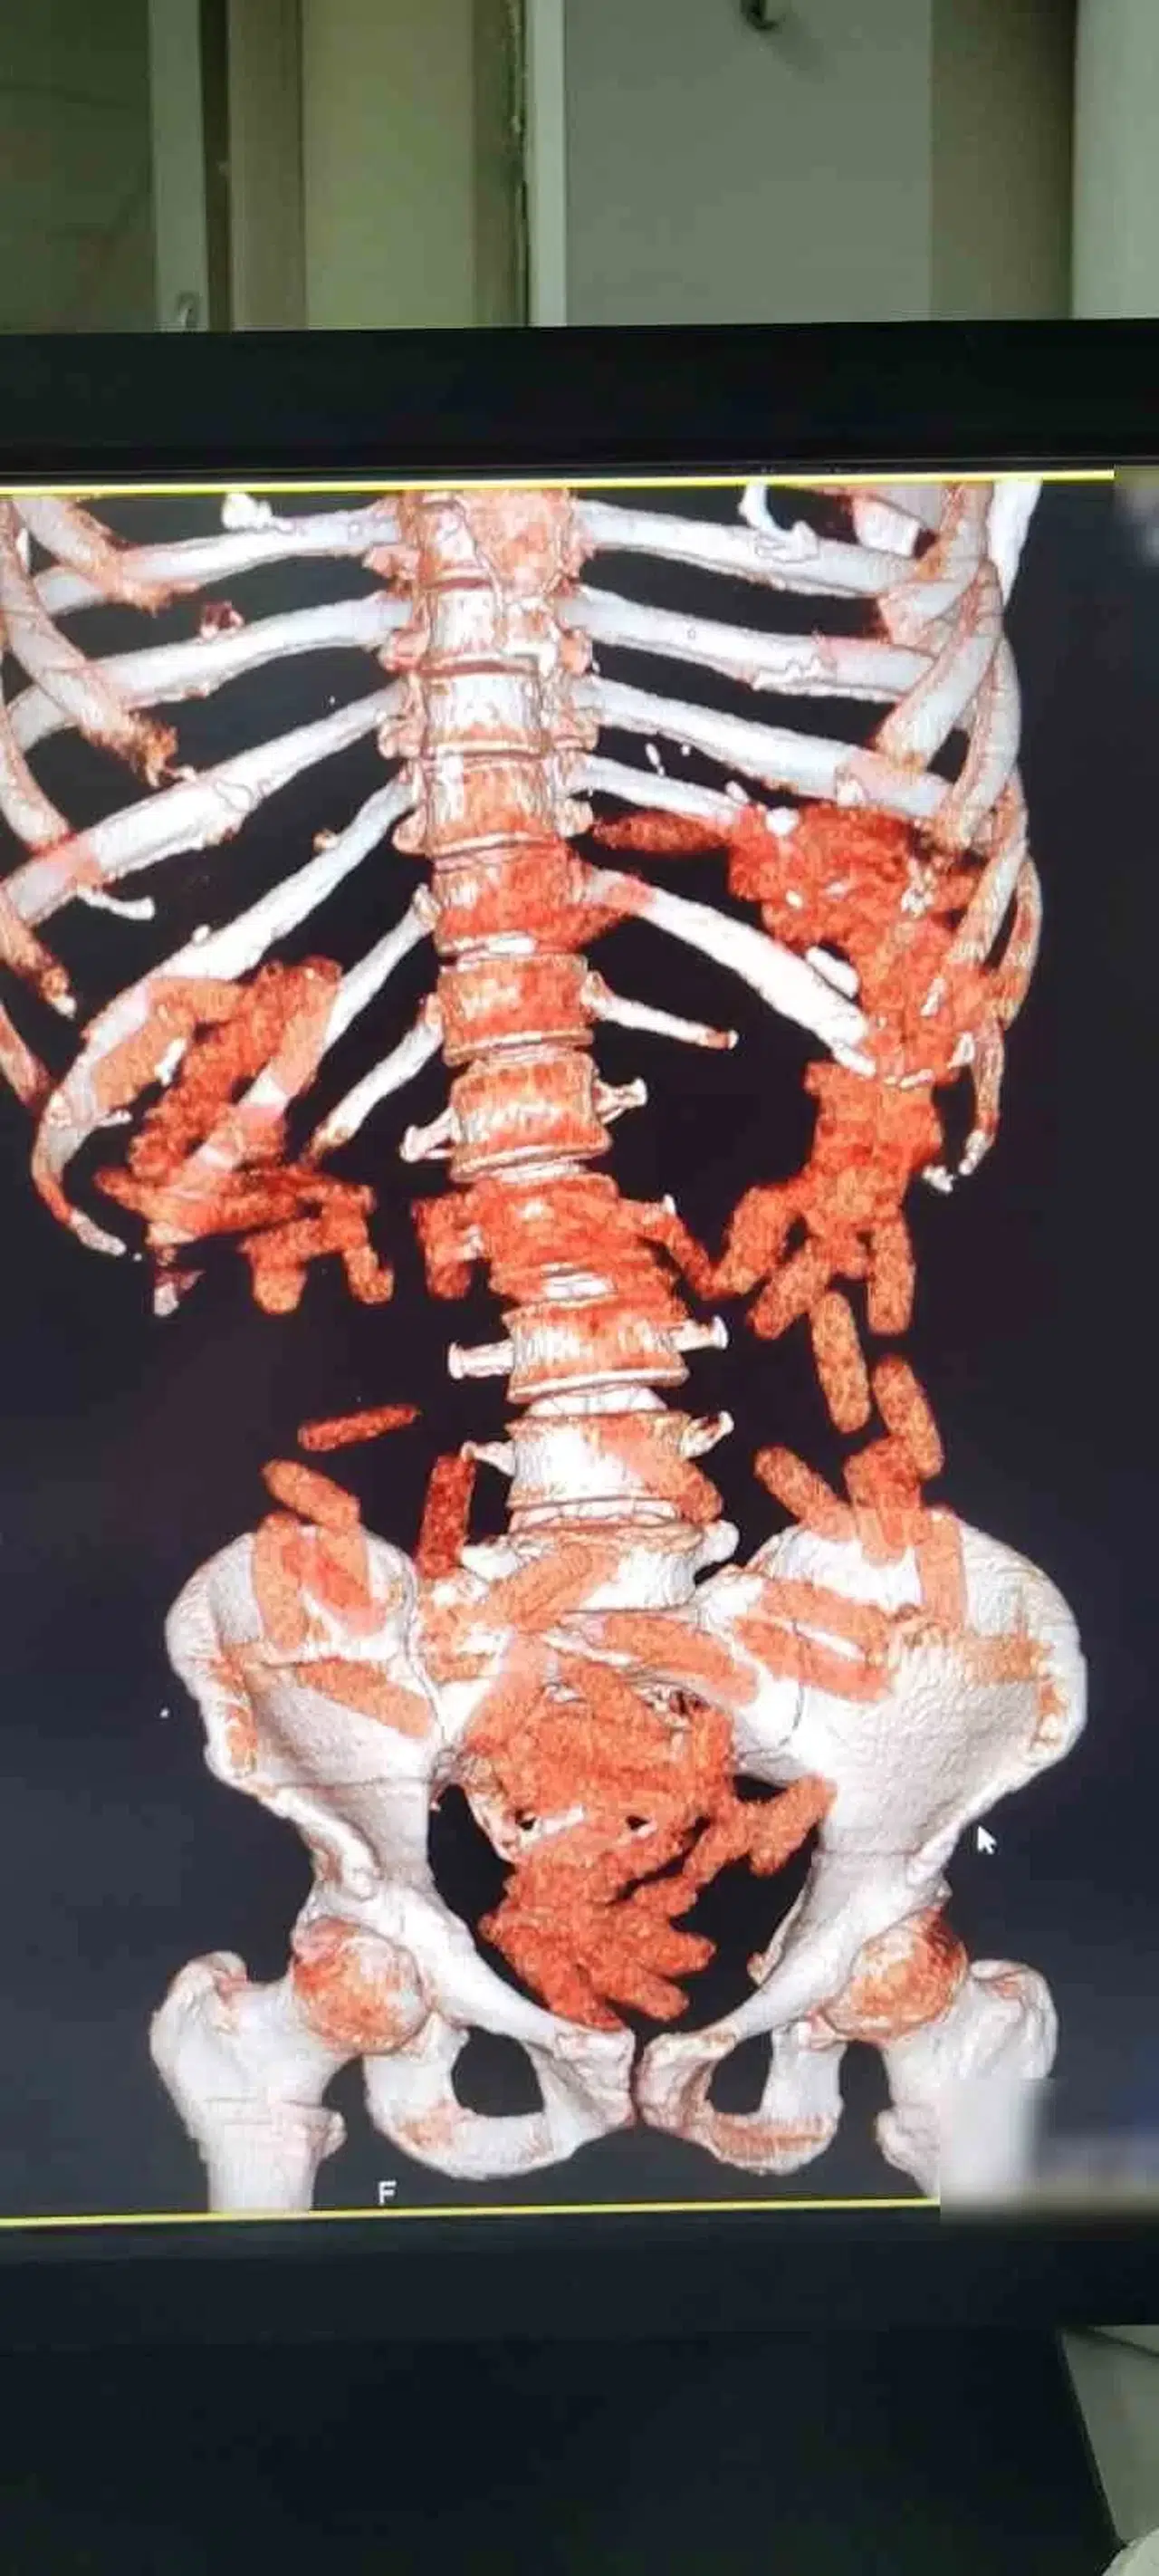

Kayseri’de polis ekipleri tarafından yapılan çalışmalarda 2 şahıs yakalanırken, şahıslardan birinin midesinden ve bağırsağından 88 kapsül halinde 974 gram uyuşturucu madde ele geçirildi.

Edinilen bilgiye göre, Kayseri İl Emniyet Müdürlüğü Narkotik Suçlarla Mücadele Şube Müdürlüğü ekipleri tarafından uyuşturucu madde ticareti yaptığı değerlendirilen şahıslarla ilgili çalışma yapıldı. Yapılan çalışmalar neticesinde yakalanan A.G.’nin (36) yapılan iç beden muayenesinde mide ve bağırsak bölümünde 88 kapsül halinde toplam 974.52 gram uyuşturucu madde tespit edildi. Öte yandan, A.A.’nın (34) yapılan üst aramasında; 2,7 gram uyuşturucu ve 76 adet narkotik hap ele geçirildi.